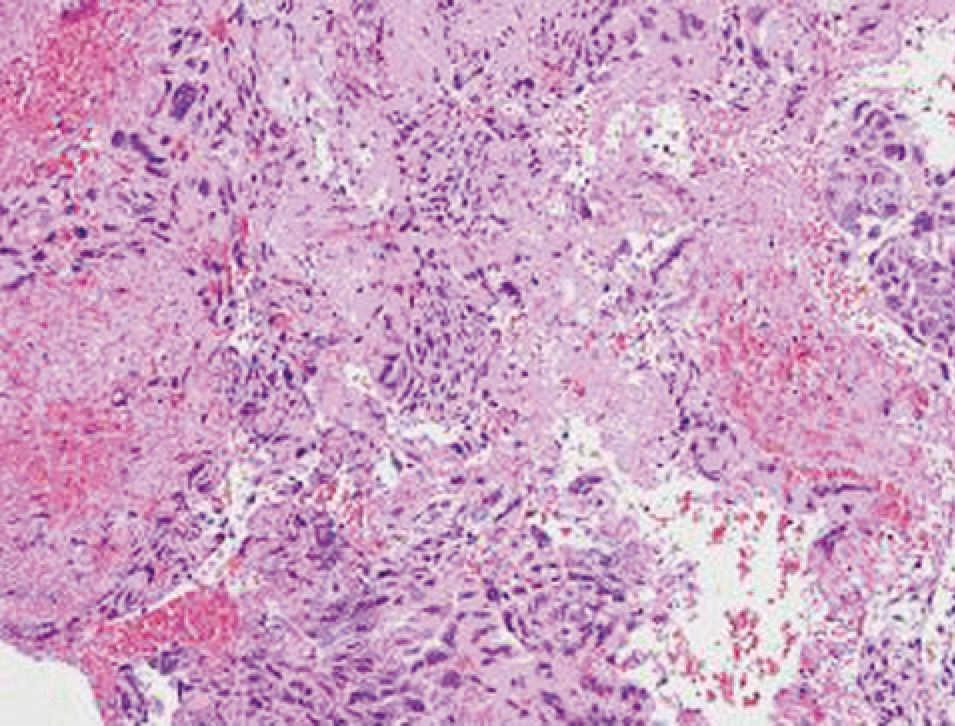

Coriocarcinoma gestacional: este es el tipo más común de neoplasia trofoblástica después de un embarazo a término o un aborto espontáneo, y sólo un tercio de los casos sigue a una gestación molar. El coriocarcinoma está compuesto de células que recuerdan el citotrofoblasto temprano y el sincitiotrofoblasto, sin embargo, no contiene vellosidades. Este tumor de rápido crecimiento invade el miometrio y los vasos sanguíneos para crear hemorragia y necrosis. El tumor miometrial puede diseminarse hacia afuera y hacerse visible en la superficie uterina como nódulos oscuros e irregulares. Las metástasis con alguna frecuencia se desarrollan temprano y por lo regular se transmiten por la sangre. Los sitios más comunes son los pulmones y la vagina, pero el tumor puede viajar a la vulva, los riñones, el hígado, el cerebro, los ovarios y el intestino. Los coriocarcinomas suelen ir acompañados de quistes de teca-luteína ováricos.